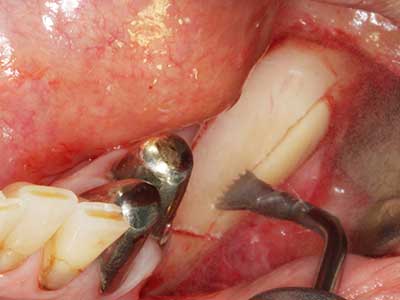

Indikation: Nervnahe Präparation

Wie bereits erwähnt lassen sich auch im Bereich der chirurgischen Zahnerhaltung Indikationsgebiete für die Piezochirurgie finden. Durch die Verwendung von speziellen Arbeitsspitzen wird die Darstellung der Wurzelspitze erleichtert, und gerade im unteren Prämolaren- und oberen Seitenzahnbereich lassen sich Nerven und Kieferhöhlenschleimhäute einfacher schützen. Bei undichtem apikalen Abschluss präparieren abgewinkelte Diamantspitzen zielgenau die Resektionskavität für das retrograde Wurzelfüllmaterial. Die Spitzen können durch die Ultraschalltechnik sehr grazil gestaltet sein, was Übersicht und Größe der Zugangskavität verbessert. So gehört in dieser Indikation die Anwendung der Ultraschallchirurgie zu den Standardverfahren der Wurzelspitzensresektion (Del Fabbro, Tsesis et al. 2010, Scarano, Artese et al. 2012).

Indikation: Wurzelspitzenresektion

Sollen chirurgische Eingriffe mit unmittelbarer Knochenbeziehung an empfindlichen Strukturen wie Blutgefäßen oder Nerven erfolgen, so bergen rotierende Instrumente ein erhebliches Potential an iatrogener Schädigung. Gerade bei Nervdarstellungen nach iatrogener Schädigung, oder aber im Zuge einer Nervlateralisation für resektive und rekonstruktive Eingriffe oder Implantatinsertionen können piezoelektronische Geräte hilfreich sein Knochendeckel zu präparieren und nervnahe Hartgewebsanteile zu entfernen (Abb. 17-20). Ein leichter Kontakt des Nervstrangs zur Piezospitze bleibt dabei in der Regel folgenlos – allerdings kann eine unvorsichtige Vorgehensweise mit sägeartigen Bewegungen bzw. Ansätzen bei noch vorhandener knöcherner Unterlage durchaus temporäre oder aber auch permanente Nervschädigungen verursachen. Das Risiko einer solchen Schädigung wird jedoch als wesentliche geringer eingeschätzt als unter Anwendung von Säge- oder Fräsinstrumenten (Pereira, Gealh et al. 2014).